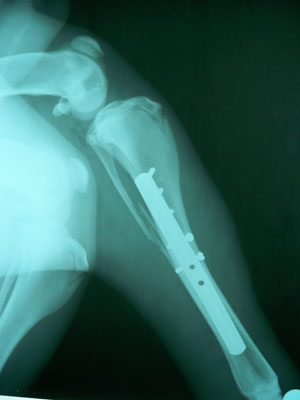

Μετά από την ανάταξη του κατάγματος τοποθετήθηκαν συμπιεστικά στην πρόσθια επιφάνεια 2 κοχλίες με σταυρωτή κεφαλή και στην έσω επιφάνεια τοποθετήθηκε μεταλλική πλάκα 3,5mm μήκους 14cm με 5 κοχλίες στο άνω καταγματικό άκρο και 4 στο κάτω άκρο.